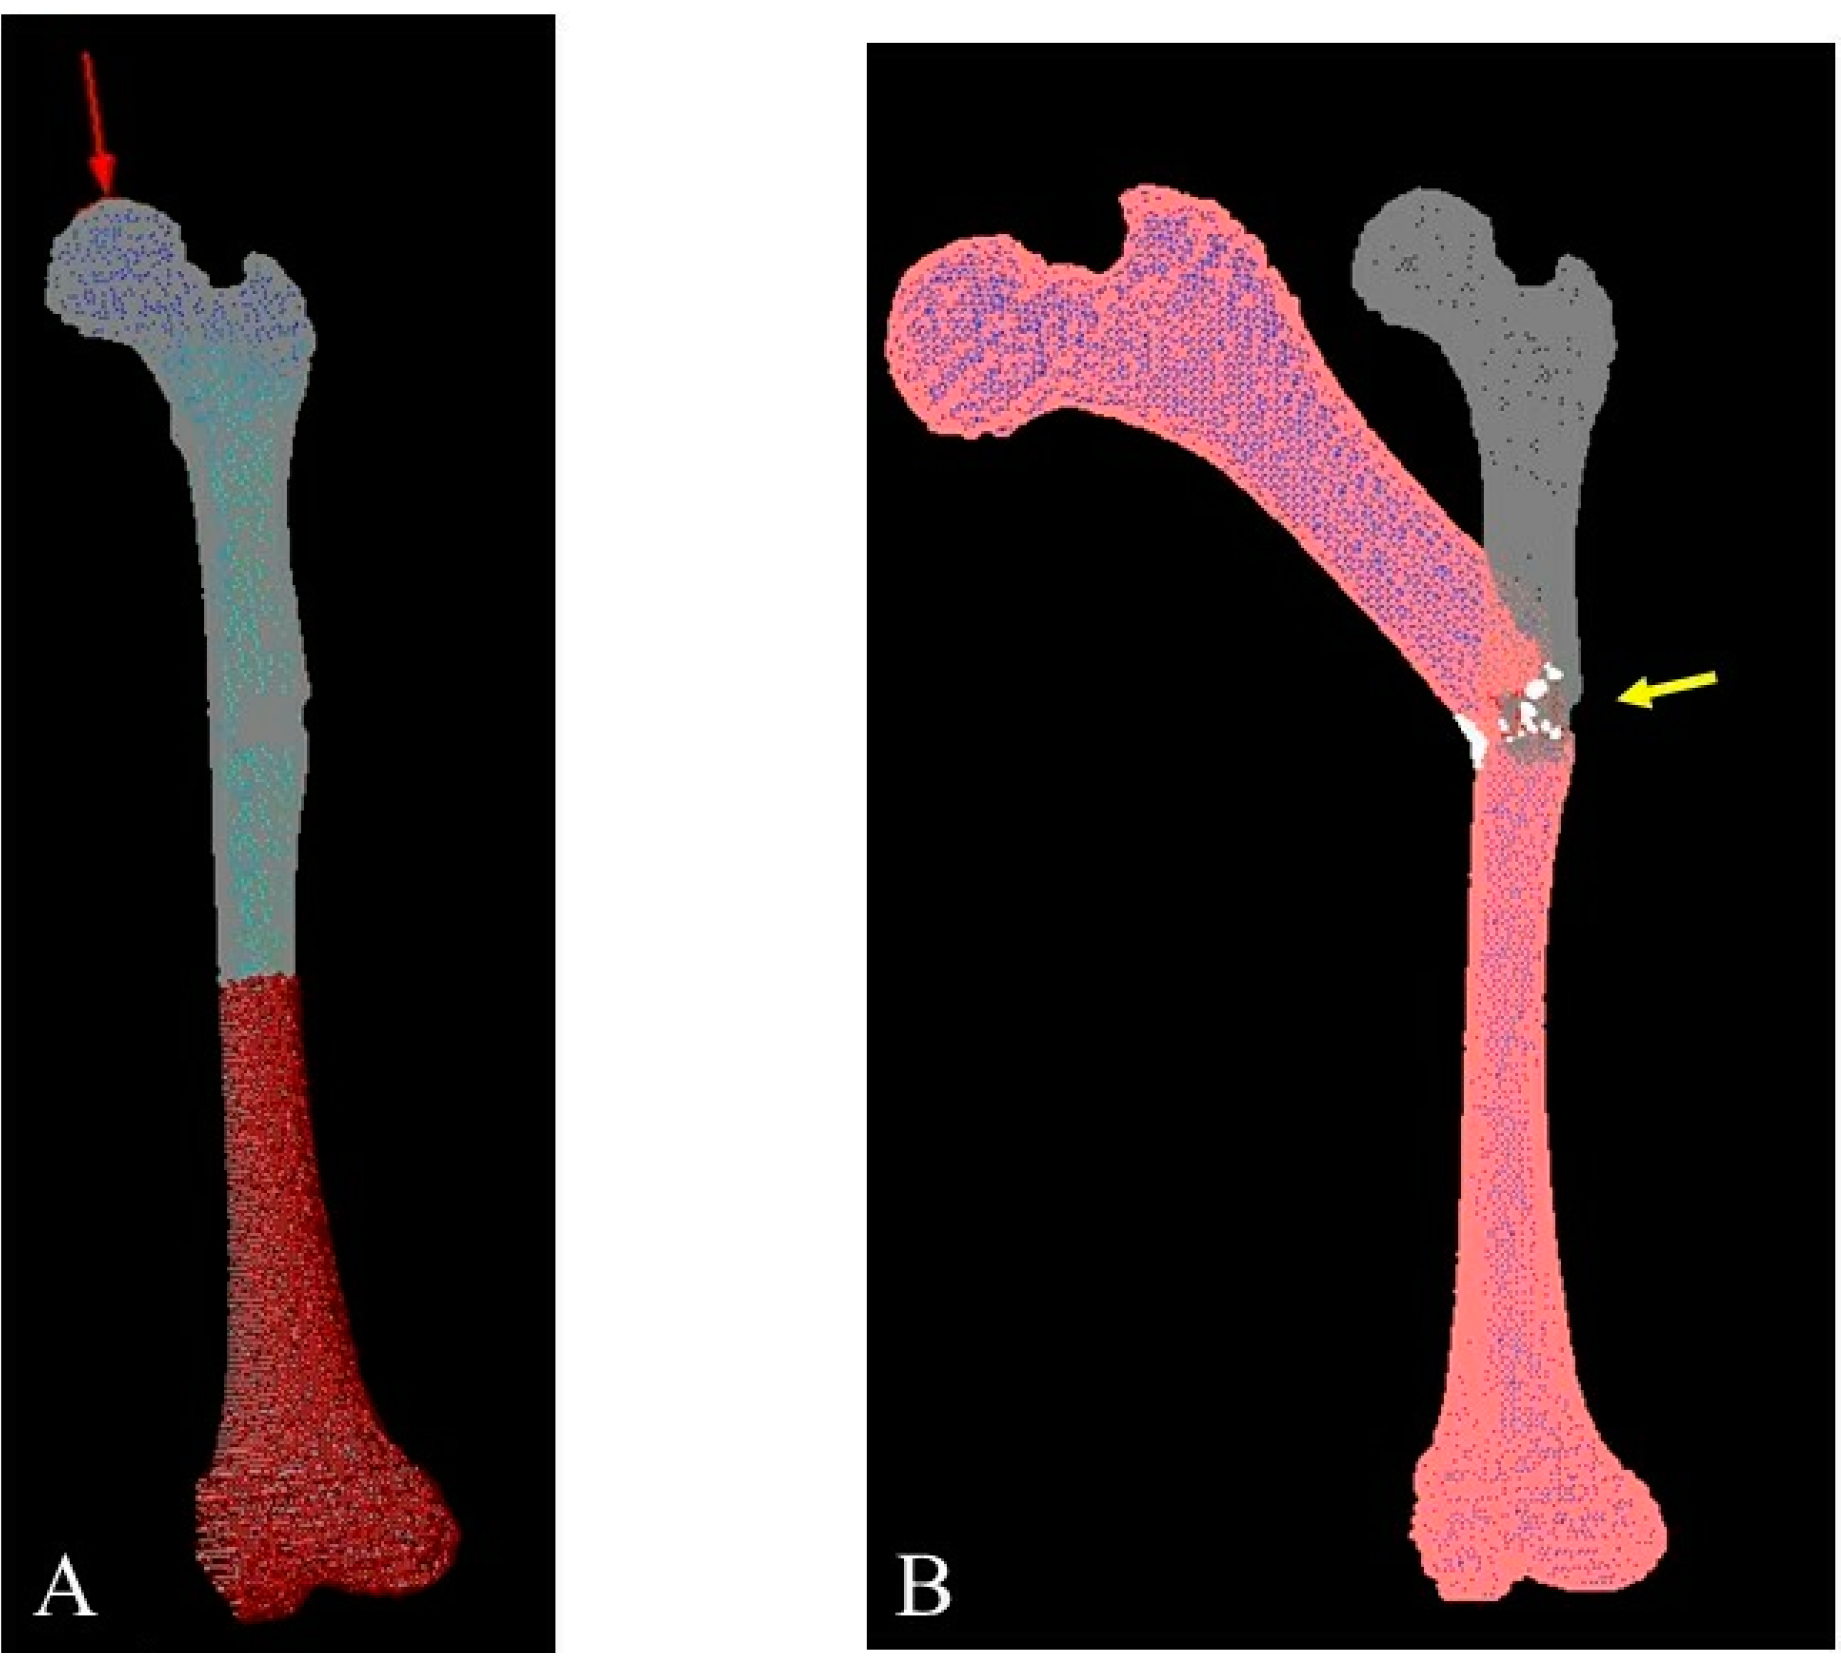

- Clinical and radiological evaluation of the osteoid osteoma.

- FEA to predict bone mechanical properties after the bone resection with the decided method, modified by tumor dimensions.

- Tumor resection and femoral stabilization, according to results of FEA.